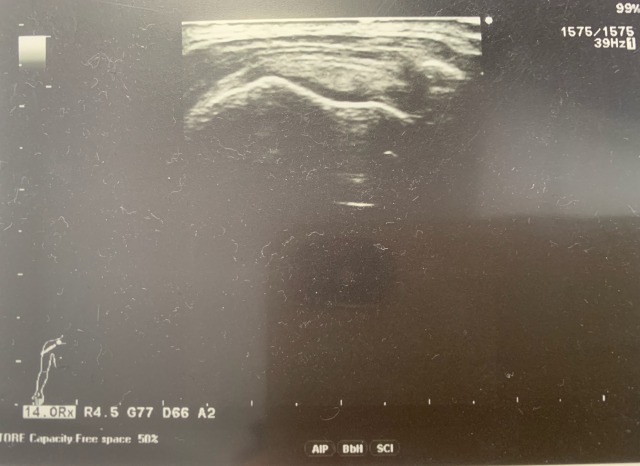

まず、問診をして、レントゲンで骨を、エコーで腱板をみました。

こちらはエコーで見た腱板の状態です。